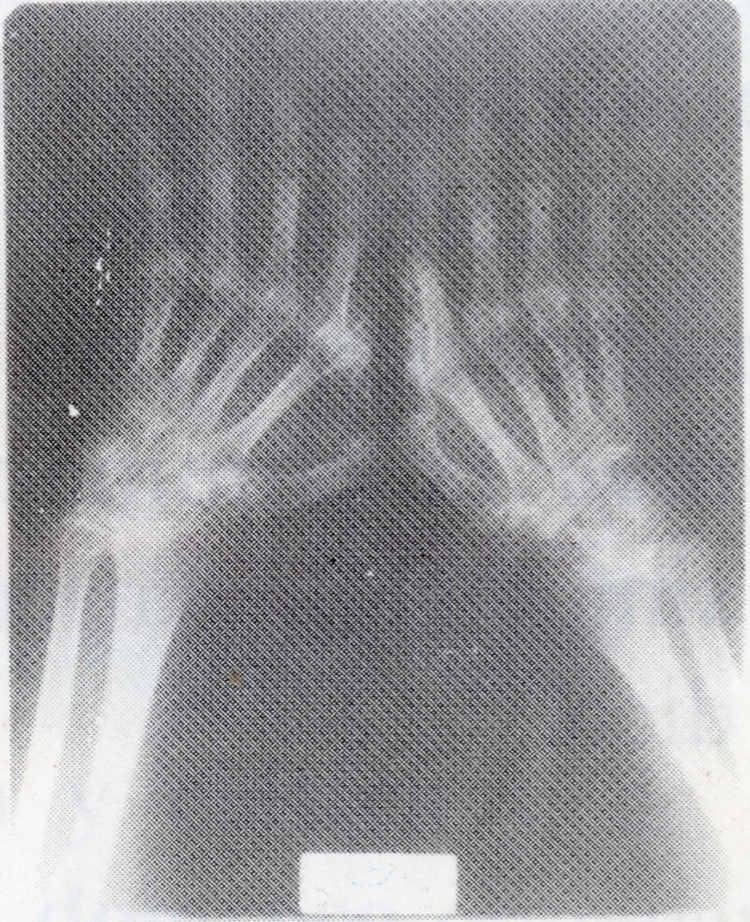

TRATAMIENTO DE LA ARTRITIS REUMATOIDE MEDIANTE RCE

Bozidar Konjevic, descubridor de la RCE, padeció esta enfermedad durante 25 años hasta su invalidez total certificada. Por este motivo desarrolló esta técnica con la que recuperaría la movilidad total y su salud. La RCE ha logrado la remisión de esta enfermedad que se considera incurable. Las radiografías muestran la gran mejoría de un paciente tras cuatro meses de tratamiento.

ANTES

DESPUÉS